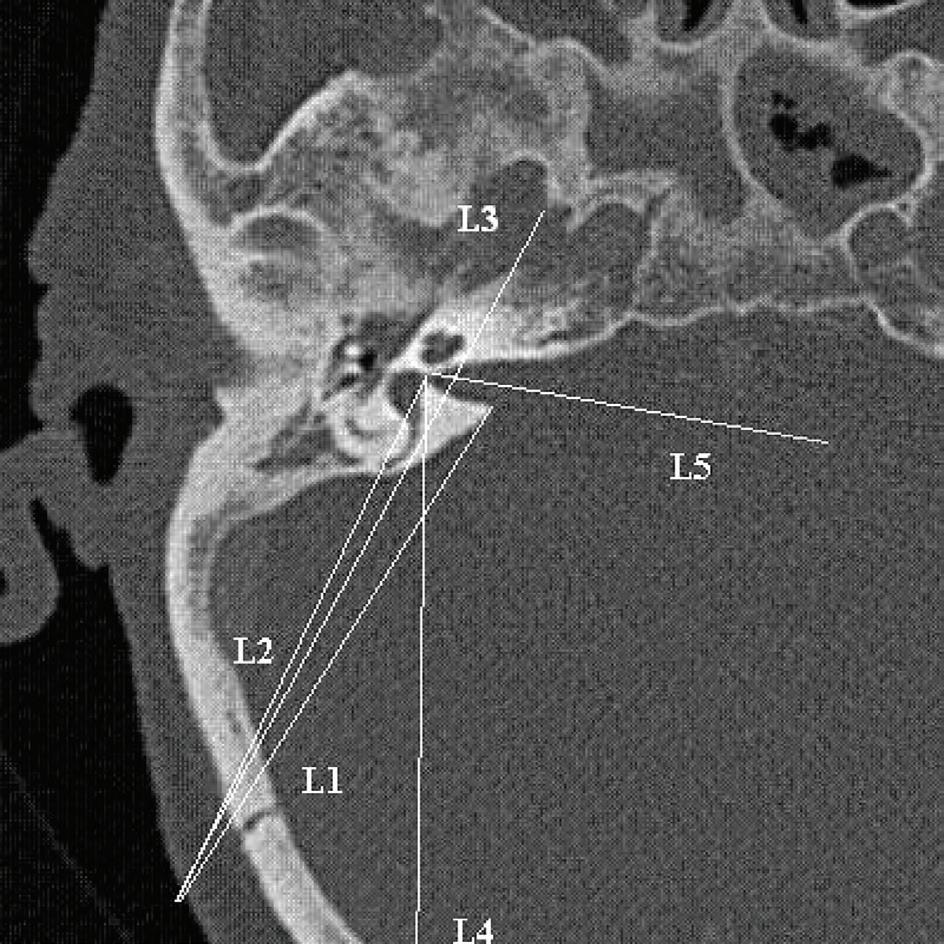

All CT scans were obtained from a 16-slice scanner CT machine (Siemens; Munich, Germany), with 0.6 mm between two slices, in the Amir-Alam University Hospital affiliated with Tehran University of Medical Sciences. The CT scans were not obtained for this study but rather for other indications. In the CT scan, the axial plane that showed the common crus of the posterior semicircular canal (figure) with better IAC visualization was selected.

Five lines were drawn and four angles and three distances were measured. Definitions of angles and distances are provided in table 1. The incision size used in the retrosigmoid approach was assumed to be 4 cm. 3 Pneumatization of bone between the IAC and posterior semicircular canal was presumed positive if air cells were visualized in this area. Pneumatization of different parts of the mastoid was evaluated to indicate extent of air cells and expressed as the percentage of presence of air cells in this compartment of temporal bone.

Descriptive data regarding the anatomy and the mastoid pneumatization of the groups appear in table 2.

IAC exposure by drilling. P1 indicates the maximum proportion of IAC that can be exposed by drilling while preserving the posterior semicircular canal. Range of the mean P1 was 0.53 to 0.64 in the three groups, and the average was 0.61 ± 0.09 (table 3). This proportion of IAC was not significantly different between the three groups (p > 0.05). Maximum exposure (0.82) was observed in normal temporal bones (with no otitis or vestibular schwannoma). Pneumatization of the posterior or anterior petrous apex or the extent of mastoid pneumatization was not related to this exposure (p > 0.05). In patients with vestibular schwannoma or otitis, no significant difference was observed between the affected and normal side (p > 0.05).

Posterior semicircular canal drilling probability. In all groups of patients, the A1 angle was wider than the A2 angle, indicating that drilling from the porus to the fundus of the IAC is not achievable without removing the posterior semicircular canal (table 3). We also discovered that A1 was always wider than A2, except in one temporal bone. These angles were similar in temporal bones with different pathologies (p > 0.05).

Proper incision site. L4 is drawn from the fundus to the most posterior point of the posterior semicircular canal to achieve proper incision and full exposure of the IAC while preventing canal trauma. The median distance of the posterior incision border was 65.2 ± 11.1 mm (range: 45 to 88.5 mm).

26 www.entjournal.com ENT-Ear, Nose & Throat Journal January/February 2018

KOUHI, ZARcH, POUyAN Figure. This CT scan of the axial plane shows the common crus of the posterior semicircular canal.

Table 1. Description of parameters used in this study

Parameter

Lines Description

L1 From porus of IAc to most posterior incision site

L2 From fundus of IAc to most posterior incision site

L3 Tangential to posterior semicircular canal from most posterior incision site

L4 From fundus to most posterior point of posterior semicircular canal

L5 IAc vector

Angles

A1 Angle between L1 and L2

A2 Angle between L1 and L3

A3 Angle between direction of posterior semicircular canal and midline in coronal plane

A4 Angle between L5 and L3

Distances

D1 From meet point of L4 to calvaria to retroauricular sulcus

D2 From fondus to porus

D3 From meet point of L3 and IAc to porus

P1 D3/D2

Endoscope vision vector. The mean A4 angle was 103° (standard deviation: 11.96°; range: 76.5 to 128.7°). In 56% of temporal bones, this angle was <105°, which means that even with a 30° endoscope, the fundus cannot be visualized (assuming a 45° visual width and a 30° midline vision vector). However, in >91% of the cases, the fundus was observed using a 45° endoscope.

The possibility of CSF leaks. In 15% of temporal bones, pneumatization of the bone between the IAC and the posterior semicircular canal was evident. This finding meant that by drilling this area, it was possible to create a tract for CSF leakage. This area of pneumatization was not correlated with the extension of mastoid pneumatization (p > 0.05).

Two-sides correlation. Table 3 shows a good correlation between the two sides of the same patient and between the area of pneumatization and pathology.